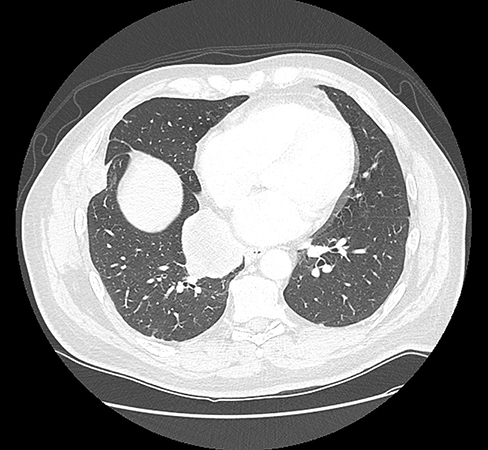

Clinical History: A 59-year-old male, never smoker, with no prior cancer history, presented with chest pain. The chest CT scan revealed a 5.5 cm solid right infrahilar lung mass (Figure 1). Representative H&E images showed undifferentiated high-grade tumor with marked necrosis, abundant mitoses, and apoptotic bodies (Figure 2). The tumor cells showed high N/C ratio, molding, and dispersed chromatin (Figures 3 and 4). Immunohistochemistry (IHC) was diffusely positive for keratin (OSCAR) (Figure 5), diffusely positive for CD56 (Figure 6), and negative for pan-cytokeratins AE1/AE3 and CAM 5.2, chromogranin, synaptophysin, INSM1, TTF-1, CD45, SOX10, S100, Melan A and HMB45. Ki67 proliferative index was more than 90%. Next-generation sequencing revealed 38 mutations including a BRAF mutation, along with abundant G>A, C>T, GG>AA, and CC>TT transition mutations, indicating a UV-exposure mutagenesis.